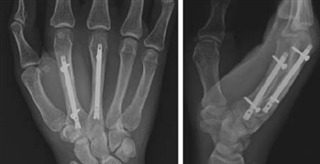

文献1】より(a) 銃撃による第5中手骨骨幹部の粉砕骨折の術前X線写真。 (b) 非観血的整復および経皮的ピンニング後の術中透視像、および(c, d) 術後3週および23週のX線写真。骨折の癒合が進行し、骨のアライメントも良好である。

文献1】より